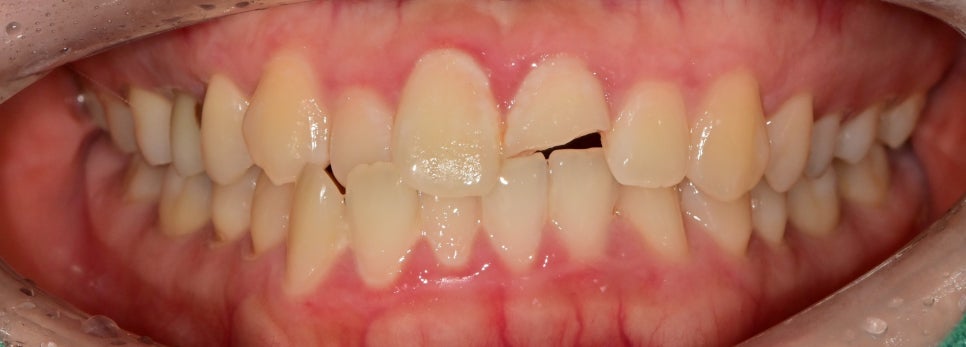

외상에 의해 제일 큰 앞니 부분이 파절되어 내원하셨습니다.

육안상으로 보았을 때 파절 범위가 컸고

무엇보다 시린 증상을 호소하고 계셨습니다

치아머리 부분의 절반 정도 파절이 되었고

외상 당시 충격으로 치아 인대 부위의 손상이 보였습니다.

신경이 외부로 노출되진 않았지만

치아가 외부 자극에 의해 시린 증상을 느끼고 있습니다